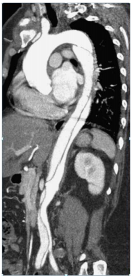

20.50歲男性病患主訴,有高血壓病史,未接受規則性之治療,3星期前有突發性撕裂性背痛至今仍舊無法緩 解。電腦斷層顯示如下圖,下列診斷及治療何者錯誤?

(A)其主動脈剝離由降主動脈至腹主動脈,但入口位於降主動脈近端處,診斷為史丹佛B型主動脈剝離 (Stanford type B) (B)需考慮手術治療 (C)症狀發生超過14天,屬於慢性主動脈剝離 (D)雖腔內血管修補術式(TEVAR)發展迅速,但手術仍以傳統開胸置換手術為主